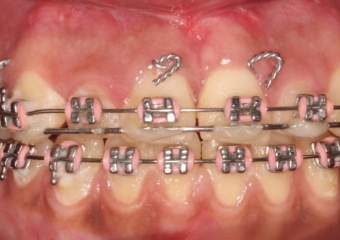

Mordida Inicial - Clínica Cliniface

Mordida Inicial